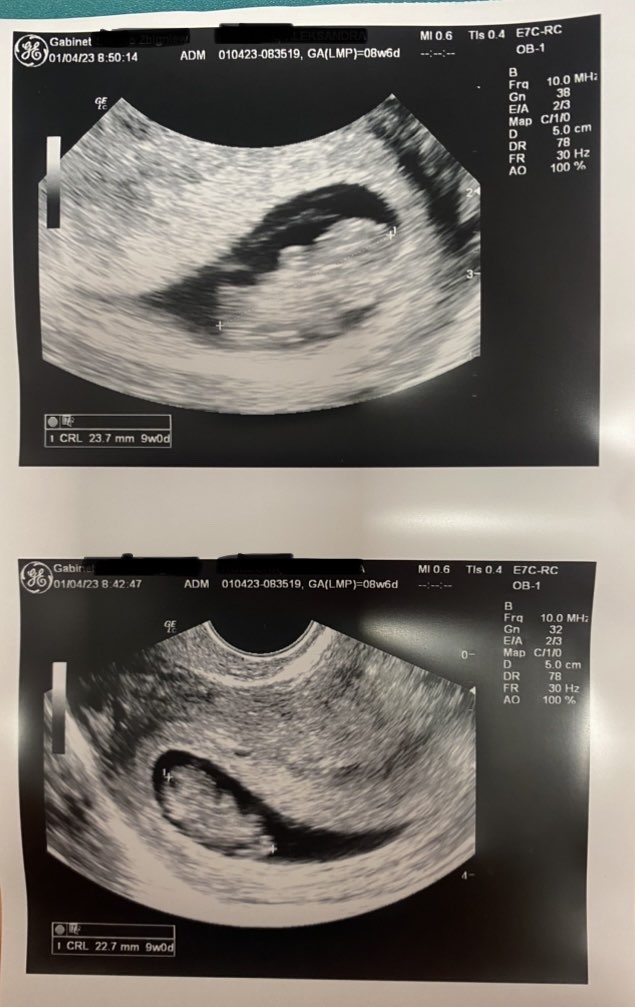

Heeeej! No cóż, jestem bardzo szczęśliwa i wizyta była mocno wzruszająca, troszke łezki poleciały. Wszystko jest w porządku, główka, raczki, nóżki są, serce bije i to nawet 160 bpm. Nawet mam nagrane jak się zarodek rusza. No cudo poprostu. Jeśli chodzi o długość, to ma 2,3 cm. Według moich obliczeń dzisiaj 8+6 ale według usg 9+0 (jeden dzień starszy) wiec wszystko wszystko dobrze. Mam założona kartę ciąży. A teraz tylko cierpliwości mi będzie trzeba, bo dopiero 27 kwietnia mam iść na prenatalne a do mojego gina 28. Nie wiem jak wytrzymam miesiąc xd

Mój dzidziutek mocno trzyma kciuki za resztę gromadki ❤️